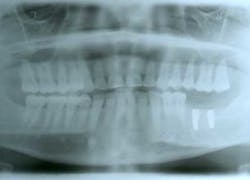

This patient presented with a missing No. 18 and hopeless No. 17 and No. 19 due to localized severe periodontal disease, recurring abscesses, and tooth migration. Severe bone loss can be seen on the initial periapical (Fig. 1) and panoramic (Fig. 2) radiographs.

Fig. 1

Fig. 2